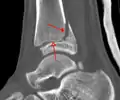

A triplane fracture of the ankle as seen on CT

CT

CT scans may be indicated when there is concern for a highly comminuted fracture or a fracture involving the joint surface.[9] This imaging may be used for surgical planning.